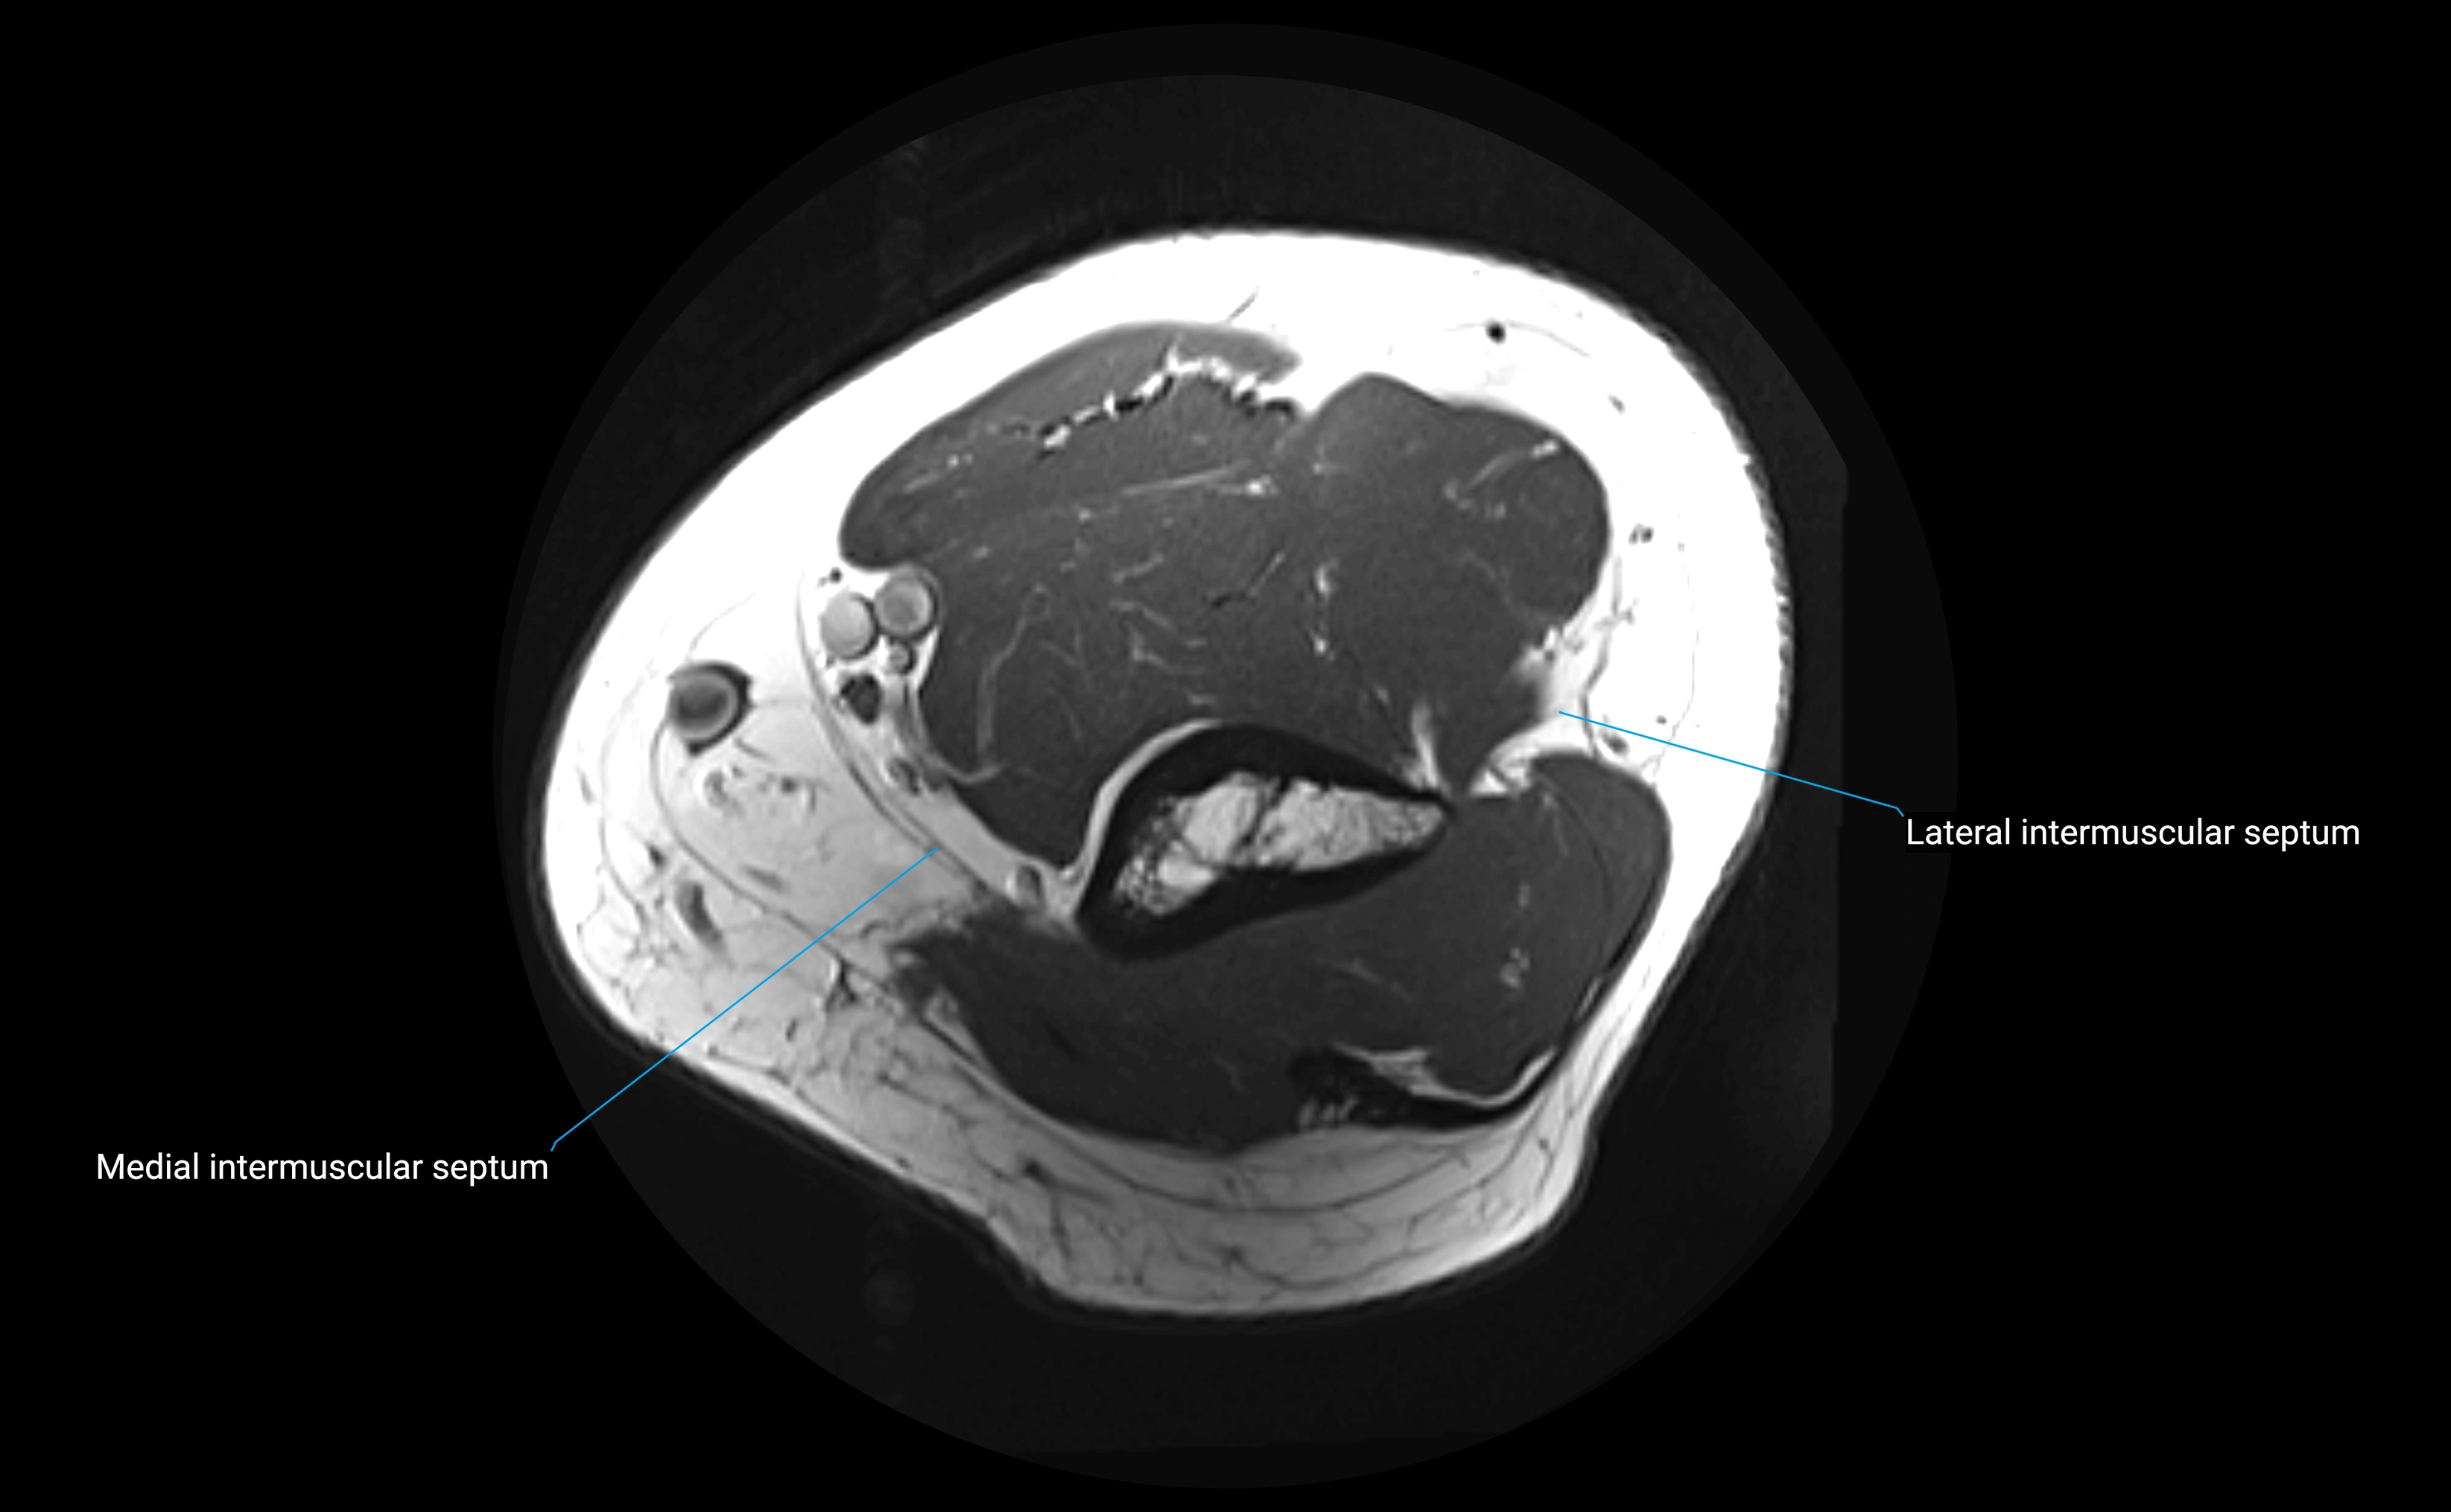

MRI Appearance

T1-weighted images:

• Ligament: low signal intensity (dark), appearing as a continuous band around the radial head.

• Adjacent fat and marrow: bright, creating contrast with the ligament.

• Thickening or disruption indicates injury or fibrosis.

• Joint capsule and synovium seen as thin low-signal lines contiguous with ligament margins.

T2-weighted images:

• Ligament: low signal (dark) with clear delineation from joint fluid.

• Fluid or edema: bright hyperintense, separating or surrounding the ligament in partial tears.

• Complete tear: discontinuity or non-visualization of ligament fibers, often with joint effusion.

Proton Density Fat-Saturated (PD FS):

• Normal: dark, well-defined band outlining the radial head.

• Partial tear: irregular or bright hyperintense signal within or adjacent to ligament fibers.

• Joint effusion and reactive synovitis appear bright and are well visualized.